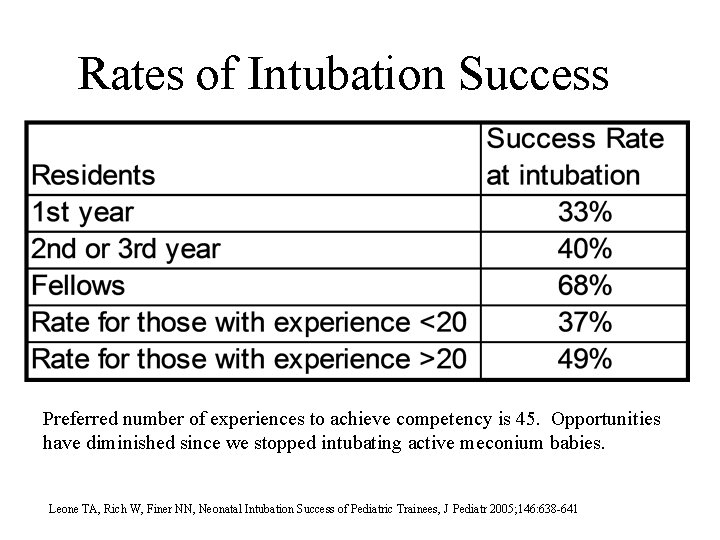

Rates of Intubation Success Preferred number of experiences to achieve competency is 45. Opportunities have diminished since we stopped intubating active meconium babies. Leone TA, Rich W, Finer NN, Neonatal Intubation Success of Pediatric Trainees, J Pediatr 2005; 146: 638 -641